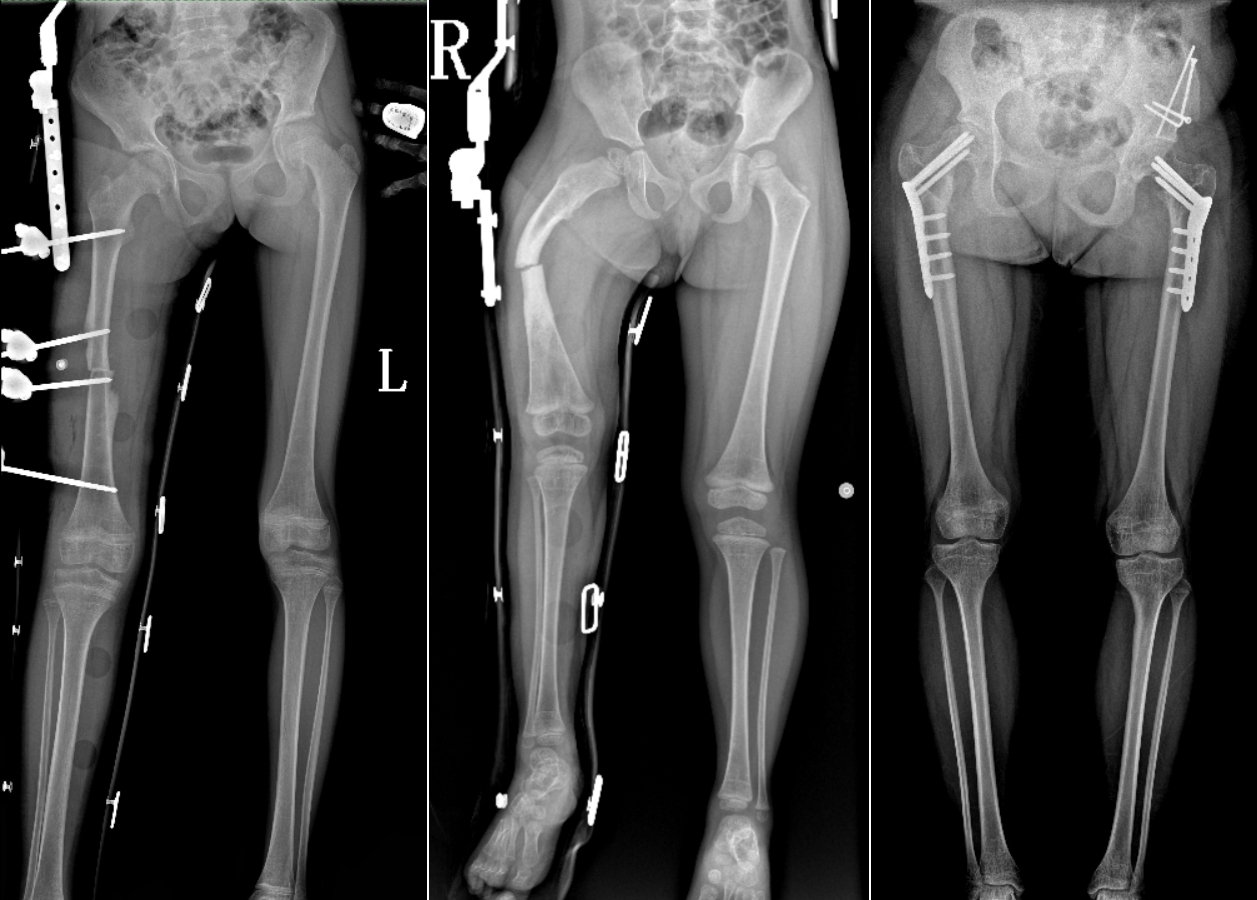

DR是臨床骨科的重要檢查手段之一。在骨科檢查中,脊柱矯形、長骨骨折、腰椎退行性病變等,需要采集脊柱、下肢全景圖像,輔助醫生臨床診斷,從而制定科學的治療方案,普愛醫療的大視野平板動態DR就像是一座橋梁,連接起現代醫療技術與當地人民的醫療需求。

普愛醫療自主研發的大視野平板動態,采用17"*34"的有效視野,一次曝光即可得到全脊柱或全下肢影像。相較于多張攝影再軟件拼接的DR設備,PLX8600解決了拼接圖像存在密度不均勻,拼接處圖像配準和放大效應等問題,給臨床帶來了真正的大視野影像解決方案。

除了常規靜態攝影外,PLX8600的大平板具備動態透視和點片功能,能夠很好地觀察復雜部位病灶,有效地抓取關鍵幀,降低患者多次攝片的概率。如:全脊柱狀態評估、長骨關節活動度、下肢靜脈造影瓣膜功能評估、消化道功能評估、脊髓造影等更多大視野臨床應用,“多面手”都能輕松應對。